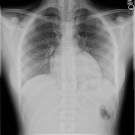

A healthy 15-year-old girl presented to a primary care acute clinic with a 1-day history of chest pain, neck swelling, raspy voice, and sore throat.